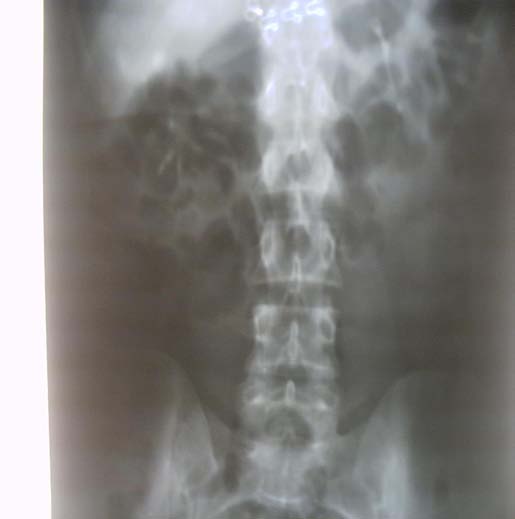

We are going to present the case of a female patient referred to our clinic with the initial ultrasound Author ? ? ? ?: Urology Department, Regional Hospital -Gjilan, UHC "Mother Theresa" Tirana, Albania, SLK Kliniken, Internal Medicine, Heilbronn, Germany. e-mail: [email protected] diagnosis of right giant renal cyst about 10 cm. Physical examination revealed no abnormalities. Given the result of the ultrasound (thick walls and small irregularities) and the possibility of a complicated cyst, we decided to investigate the matter further, and programmed the patient for an enhanced abdominal computer tomography with intravenous contrast.

The enhanced CT images revealed a right kidney cystic mass, with a 10 cm diameter, thick irregular walls with contrast enhancement, hyperdens content, and no pathological lymph nodes or distant metastases. The diagnosis was a Bosniak IV.